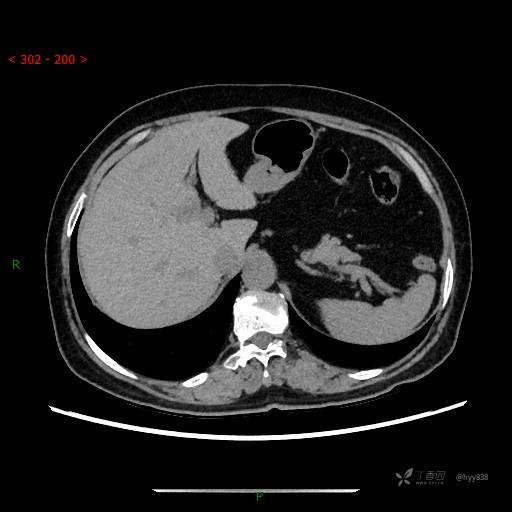

上腹部CT平扫